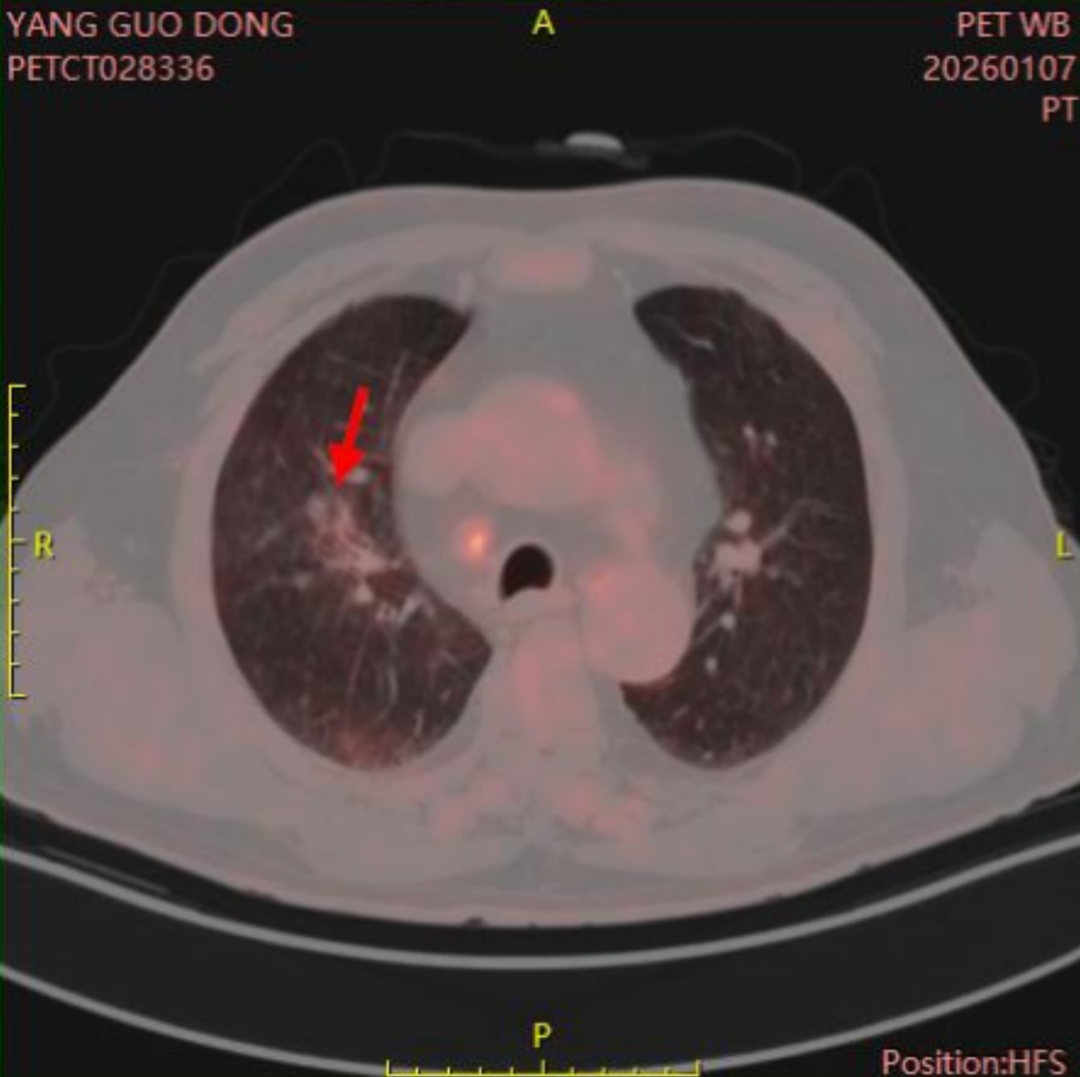

治疗前后影像学的客观对比,最能说明患者治疗情况:

杨先生肿瘤大小变化:

2025年8月(治疗前):61mm×51mm

2025年9月(首次介入后):27mm×14mm

2025年10月:25mm×9mm

2025年11月:24mm×8mm

2025年12月:19mm×8mm

2026年1月:肿瘤内无活性

(患者目前肺内肿瘤已无活性)

肿瘤最大径从61mm缩小至19mm,缩小约70%,且肿瘤内部已无活性。达到了部分缓解(PR)的标准。这种持续的缩小趋势,表明治疗起到了明确效果。